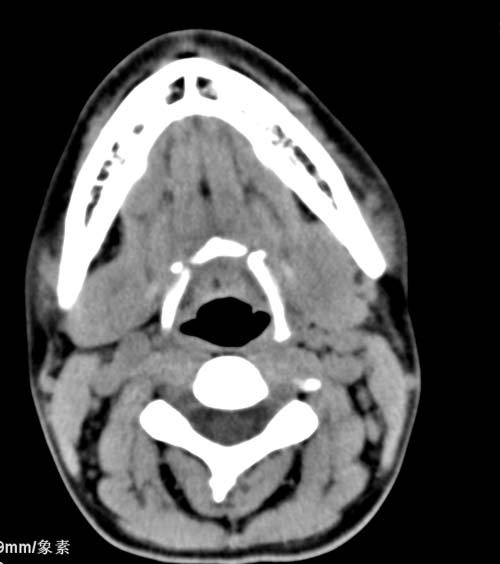

标题: CT22662:女 23 自述双侧颌下腺肿大年余 近来疼痛 左侧明显 [打印本页]

标题: CT22662:女 23 自述双侧颌下腺肿大年余 近来疼痛 左侧明显

见双侧颌下腺略肿大  未见结石及钙化 考虑双侧慢性炎症 ?请指教